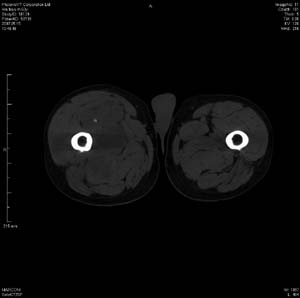

男 63岁 右大腿无痛性肿块11年,x片右大腿软组织肿块影,余无明显异常.ct值-13__239hu

右大腿股内侧股与收肌间隙间多发囊实性占位,界清.内示斑点状钙化.局部骨质无异常.肌肉推压移位表现.

考虑肌间隙病变.可有1,神经来源肿瘤.2,血管来源病变.3,淋巴来源肿瘤.4,脂肪来源肿瘤.5,滑膜来源肿瘤.结合病史只能考虑良性占位.建议增强或mri进一步分析.

同意,病史较长,病变周围分界清晰,考虑良性病变。病灶内有多发斑点状钙化,沿肌间隙生长,血管瘤或淋巴管瘤首先考虑。